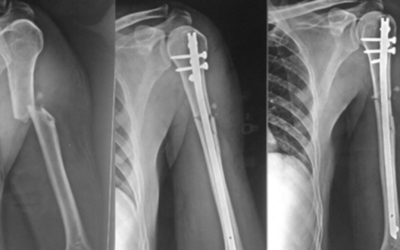

Interlocking Nail Systems Achieving Rotational Stability in Long Bone Fractures

Fractures of the long bones specifically the femur, tibia, and humerus—present unique challenges to orthopedic surgeons. Unlike small bone fractures, these injuries are subject to immense mechanical stresses, including axial loading, bending forces, and,...